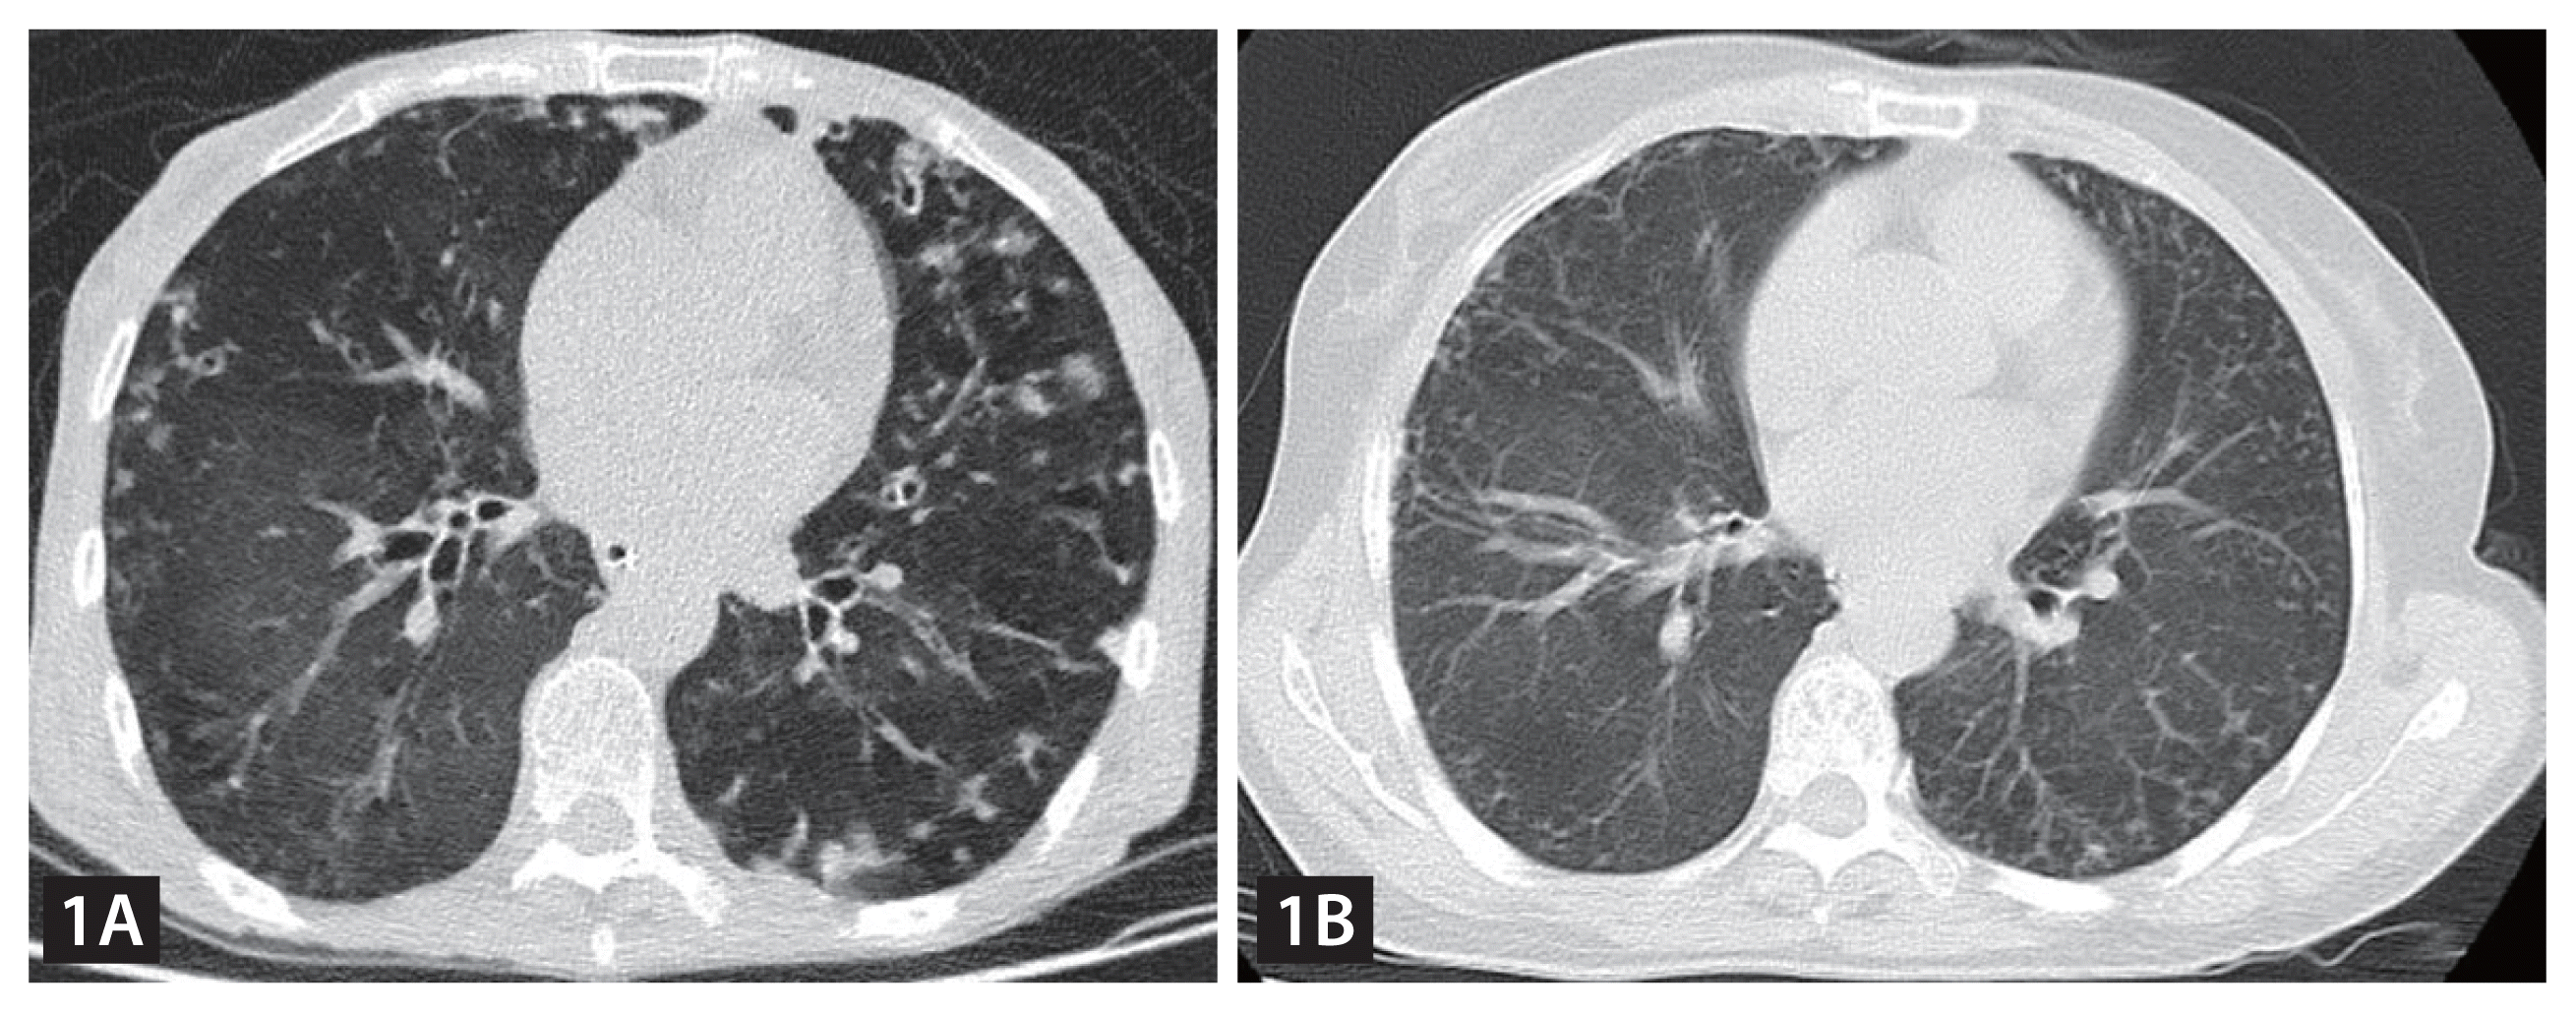

A 62-year-old woman presented with a 3-year history of recurrent wheezing, coughing, sputum production, and 10-kg weight loss. Before this hospitalization, she has had repeated hospital admissions due to the above-mentioned complaint. Skin examination revealed no abnormalities. Pulmonary auscultation revealed bilateral wet rales in the lower lung fields. Laboratory values disclosed neutrophilia (10,610/μL), normocytic anemia (7.9 g/dL), hypoalbuminemia (27.4 g/L) and elevated inflammatory markers (C-reactive protein of 41.98 mg/L), without eosinophilia (390/μL). Chest computed tomography (CT) indicated diffuse lung inflammation (Fig. 1A). She was started on antibiotic therapy, but the condition didn’t improve. Due to the history of recurrent unexplained pneumonia and poor response to antibiotic therapy, parasitic infections were suspected. Hence, multiple stool parasite examinations were performed and revealed nematode larvae (Fig. 2A). We also detected nematode larvae in sputum (Fig. 2B, Gram staining) and vomitus specimens (video). Subsequently, strongyloides ELISA blood test was executed and the result was positive. Based on the above findings, the patient was diagnosed with Strongyloides stercoralis hyperinfection syndrome. She was initiated on oral ivermectin at 200 μg/kg once daily for 6 weeks. Fortunately, her condition gradually improved over the following month. A follow-up chest CT scan showed significant improvement of the lesions (Fig. 1B). No recurrences have been observed during 2 years of follow-up.

Figure 1

Chest computed tomography (CT) scan of the patient. (A) Chest CT indicated diffuse lung inflammation. (B) Follow-up chest CT scan showed significant improvement of the lesions.